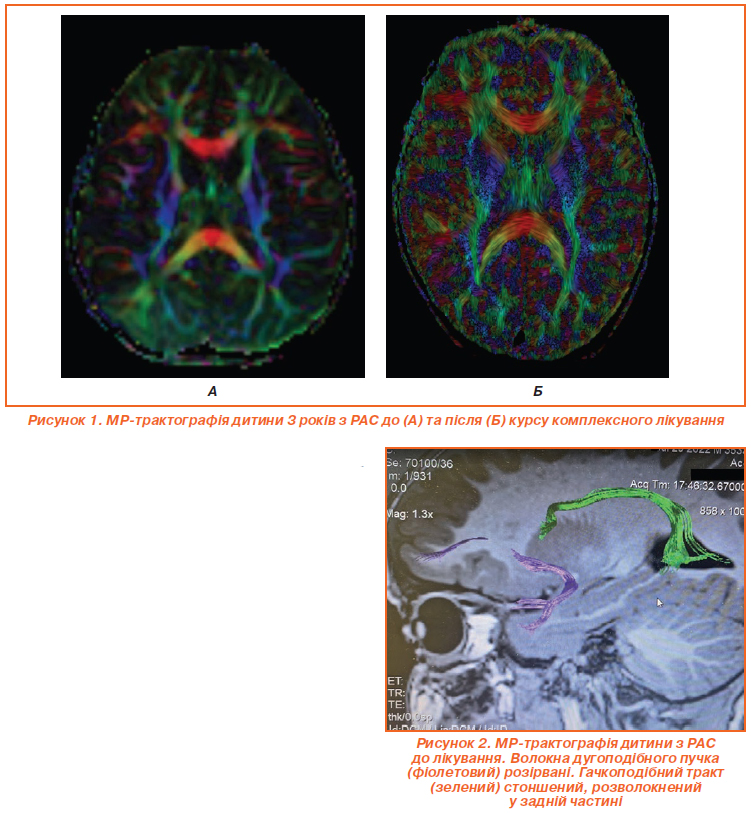

Для оцінки ефективності лікування застосовувалась МР-трактографія (рис. 1, 2). Рис. 1А відображає МР-трактографію мозку дитини 3 років з розладом аутистичного спектра (РАС) до лікування, видно характерні порушення в організації білої речовини. На аксіальному зрізі мозолисте тіло, представлене помаранчево-червоною дугоподібною структурою, виглядає стоншеним і асиметричним, з розривами трансверсальних волокон, що вказує на ослаблену міжпівкульну комунікацію, типову для РАС. Фронтальна ділянка з зеленими та жовтими асоціативними трактами, як-от superior longitudinal fasciculus, містить розірвані V-подібні структури з низькою щільністю, що корелює з труднощами в соціальній взаємодії та мовленні. У потиличних відділах візуалізуються фрагментовані inferior fronto-occipital fasciculus, а синьо-фіолетові кортикоспінальні тракти сформовані нерівномірно, що проявляється затримкою моторних навичок. Дугоподібні тракти (arcuate fasciculus) розірвані (рис. 2) та мають знижену фракційну анізотропію, що є маркером аномальної нейронної конективності при РАС.

Рисунок 1Б демонструє позитивну динаміку після курсу терапії, дані МР-трактографії вказують на поліпшення організації трактів. Мозолисте тіло стало більш цілісним і симетричним, з посиленою щільністю червоних волокон, що вказує на поліпшення інтеграції півкуль. Фронтальна ділянка містить відновлені superior longitudinal fasciculus та arcuate fasciculus з менш вираженими розривами, що сприяє поліпшенню соціальних та мовленнєвих навичок. Потилична ділянка містить відновлені inferior fronto-occipital fasciculus, які візуалізуються чіткіше. Збільшення фракційної анізотропії у дугоподібних та гачкоподібних трактах свідчить про високу нейропластичність дитячого мозку та ефективність терапії, хоча повна нормалізація потребує подальшого лікування.